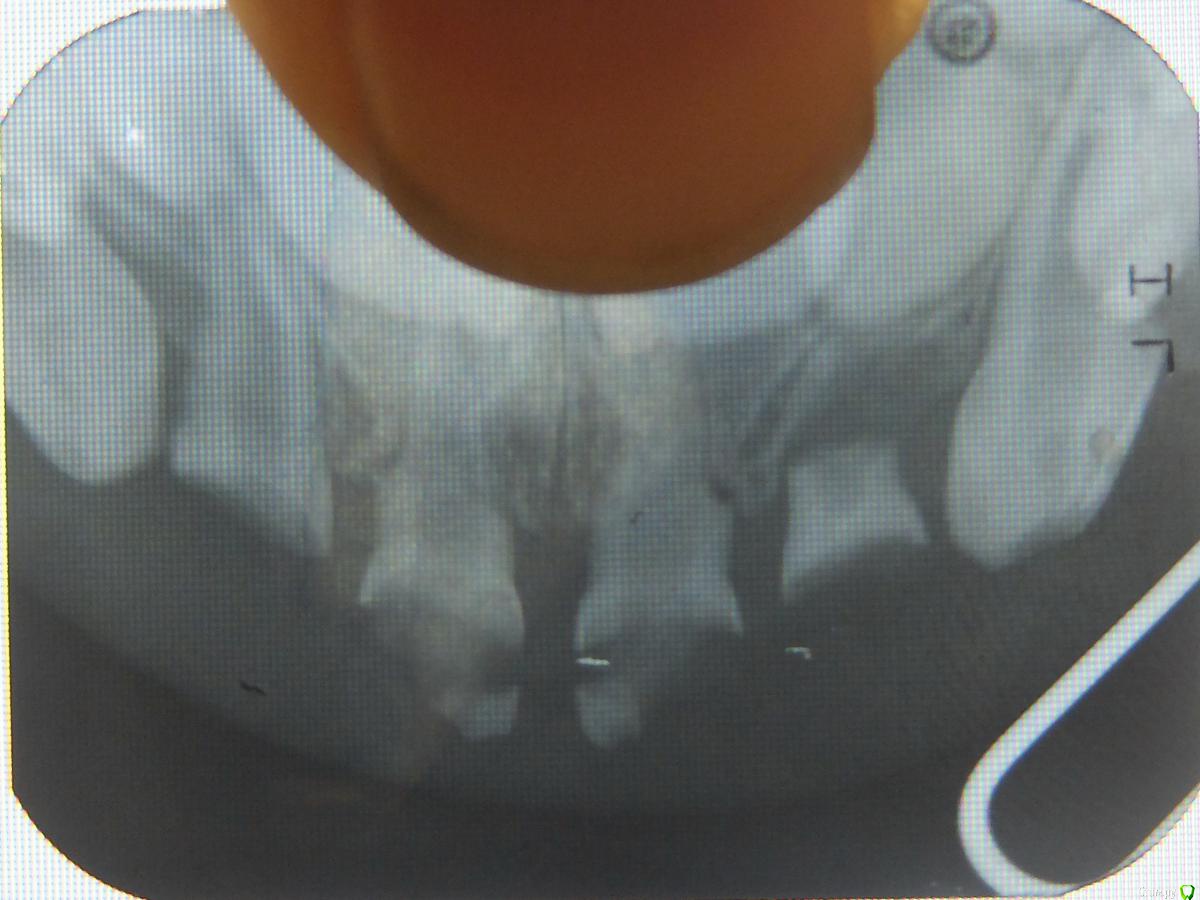

lejeboka Опубликовано 18 октября, 2017 Поделиться Опубликовано 18 октября, 2017 (изменено) Добрый день. У малыхина передние зубы рано начали портится, сделали покрытие серебром – не очень помогло. Сейчас два года и три месяца, четыре передних зуба предложили удалить (консультировались в МГМСУ на Вутетича). Так-же кариес на других зубах. Проблема в том, что у ребенка проблема с сердцем – при рождении было пять перфораций в межжелудочковой перегородке, сейчас осталась одна, 2 мм, общее состояние ребенка – отличное, в детском саду самый здоровый в группе, но кардиолог не дает добро на наркоз. На вутетича считают что лечить можно только в многопрофильной клинике, под наркозом, при наличии кардиолога и детской реанимации. В настоящее время из райполиклиники дали направление во больницу святого Владимира. Был бы рад консультации:- действительно ли необходимо удаление всех четырех передних верхних- как можно сделать удаление, какие варианты кроме наркоза- где можно провести лечение? Изменено 18 октября, 2017 пользователем lejeboka Ссылка на комментарий